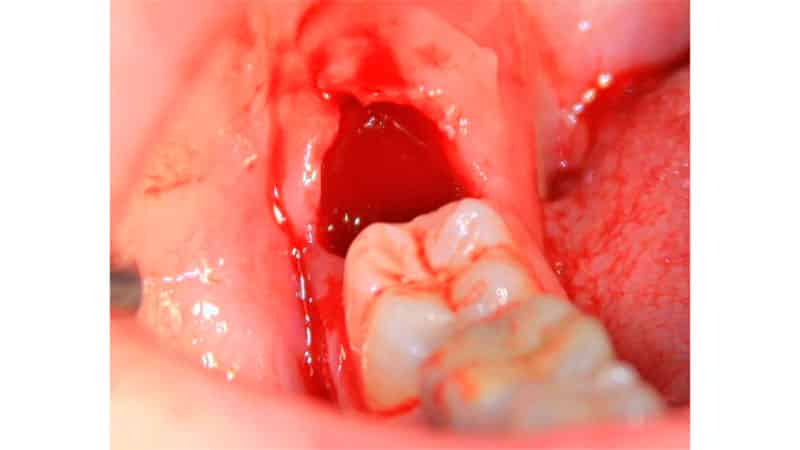

Как удаляют «мудрые» моляры

Место удаленного зуба мудрости

Сложное удаление зуба мудрости